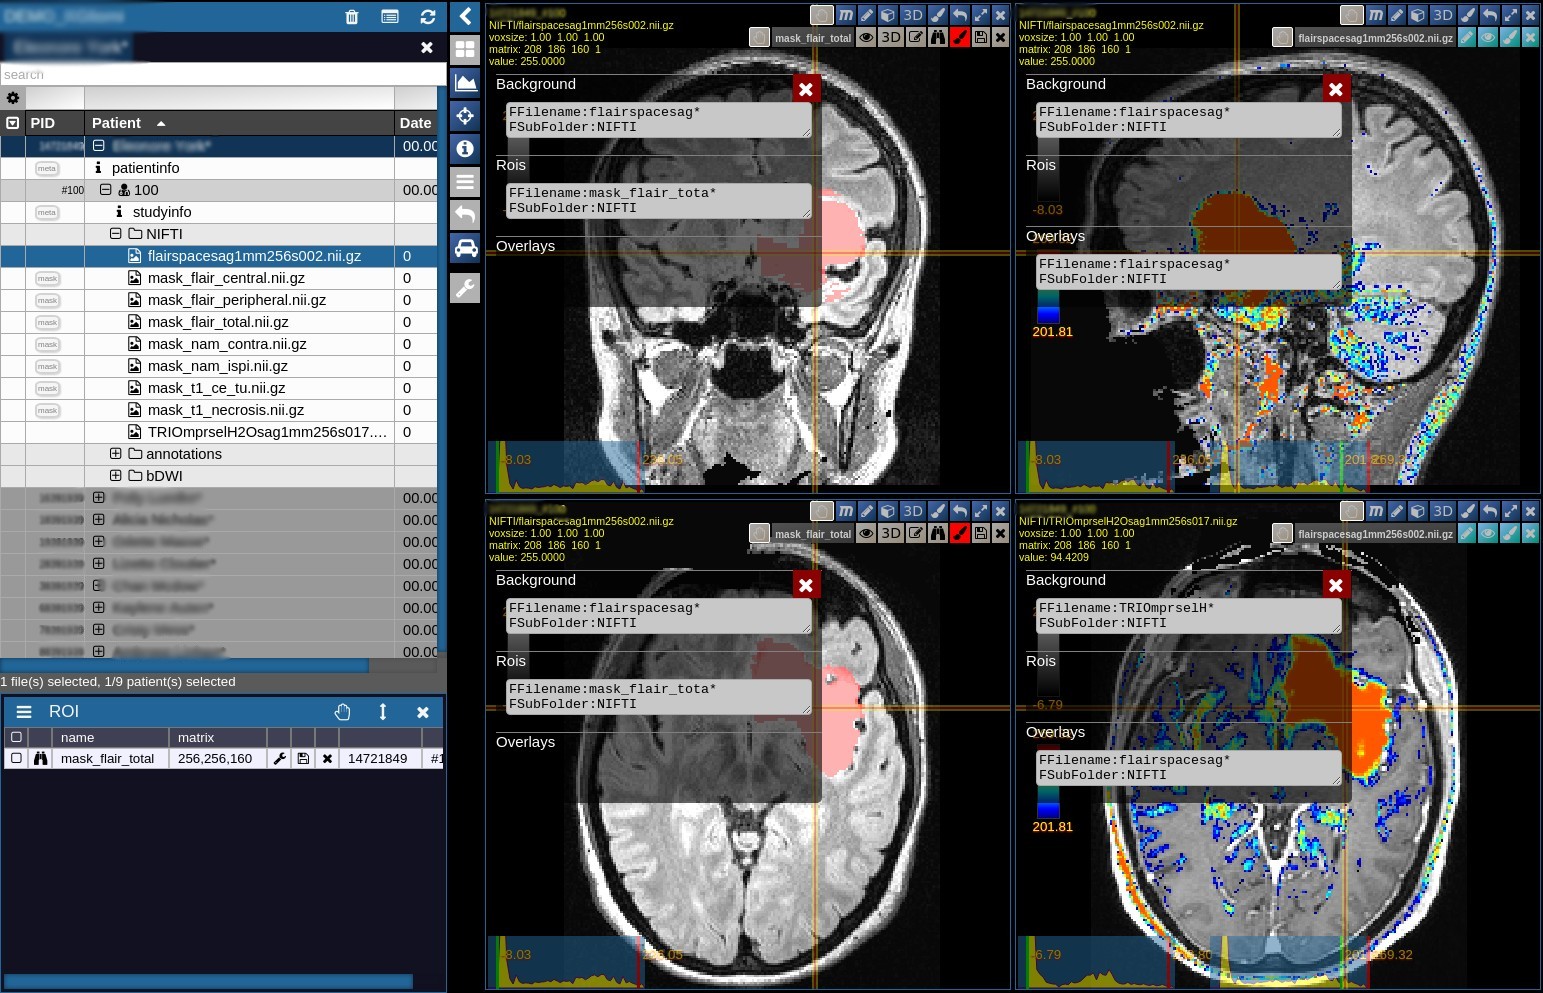

Image viewer: All standard features are available, such as correct interpretation of 3D orientation information, real-time reslicing (MPR reconstruction), slicing of different images in same voxel space, overlays and rois.

Smartloader: Define which images / metadata you want to automatically load when selecting a patient from your project, for example "Load the flair MRI scan as an orthoview and overlay with a PET image from another session", or "In a longitudinal study, load all available flair images for each visit in different sub-windows."

No matter how your data is distributed, in the web-interface everything will show up well organised at one glance, searchable, browsable and sharable to colleagues working on this project. Here, you can also set up your SMARTLOADERS to define which images should be loaded in which configuration when selecting a patient.

A new Patient, sent from a PACS, uploaded via the webinterface or mounted as a new network drive will automatically pop up in the list. You can set tags, add metadata, browse, sort, search, define groups and and start the data processing from here.